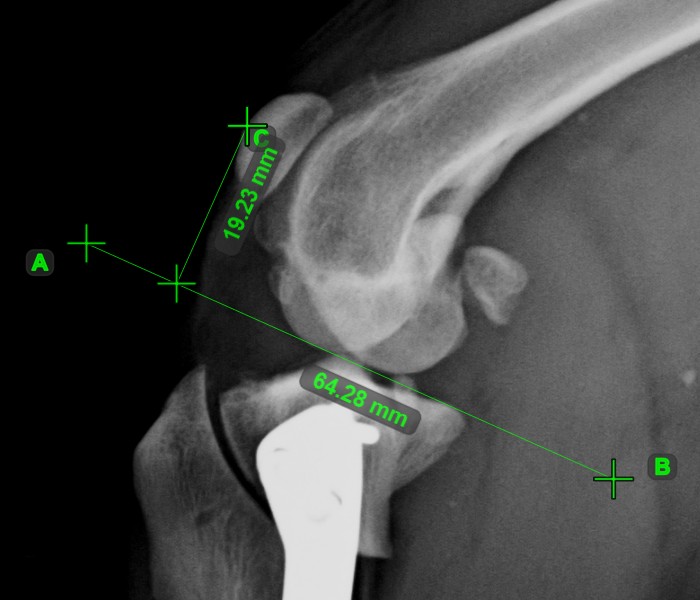

Hide/Show Measurements and Subtitles¶

The measurements and their description and subtitles can be hidden by using the Hide/Show Measurements and Subtitles button in the viewer toolbar. Depending on the active state of the measurements, the button is accordingly updated.

The button always shows the current active state of the measurements.

Change this setting individually for each measurement by using the measurement list.

All of the measurements are still visible in the viewer area, however their description and subtitles are hidden.

Additionally, the visibility of the measurements in the viewer area can be toggled by using the Menu -> Show measurements option from the Viewer menu.

Measurement Line Thickness and Label Size¶

Press the Measurement Line Thickness and Label Size button in the viewer toolbar to open the corresponding panel. Updating the line thickness and label size of the measurements in the current view overrides the global settings.

To ensure better visibility and readability of the measurements in the Viewer, simply drag the corresponding slider in the preferred direction, press on one of the available preset options, or manually enter the value in the input field next to the corresponding parameter. All of the measurements in the current view are updated automatically.

Simultaneous update to the Measurement Line Thickness and Measurement Label Size parameters is available by pressing the button connecting the two sections.